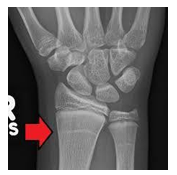

Harris Lines

•Reaction to:

-stress

-

Pathological

-Nutritional

-Emotional

Transverse

sclerotic layers in the

metaphysis

indicating times of reduced growth

Most frequently observed in the ribs and long bones particularly in

tibia

and

distal femur

.